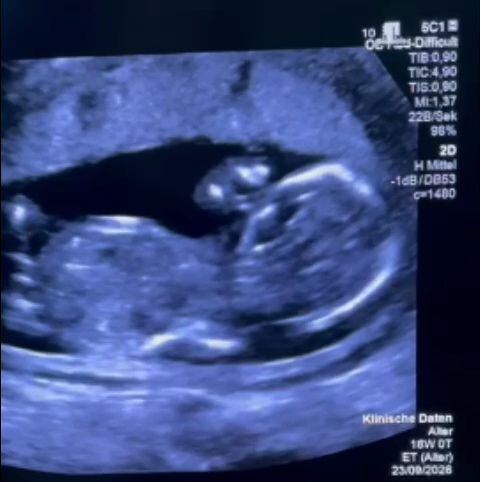

Povestea începe cu o descoperire la 12 săptămâni de sarcină: o vezică urinară mărită a fătului. Medicii au recomandat un consult de medicină materno-fetală, iar familia a căutat soluții. Familia a contactat un navigator de pacienți pentru a înțelege drepturile legale și pentru a identifica centrele medicale specializate din România. În paralel, au apelat la profesorul german Thomas Kohl, expert în domeniu. Acesta a subliniat urgența intervenției, motiv pentru care părinții au decis să încerce mai întâi în România.

Părinții au fost nevoiți să plece în Germania, unde, în ziua de Paște catolic, a fost efectuată intervenția chirurgicală de către profesorul Kohl. Acesta a menționat într-o postare pe Instagram: ”O consiliere extrem de slabă, mai ales că rezultatele tratamentelor noastre pentru această afecțiune sunt publice și disponibile gratuit”. Procedura a fost un succes, iar bebelușul a trecut cu bine de prima noapte critică.

Profesorul Kohl a montat un stent în vezica fătului. El a explicat că, dacă stentul rămâne bine poziționat, evoluția sarcinii poate fi favorabilă. Medicii europeni recomandă intervenția între săptămânile 11-16 de sarcină.